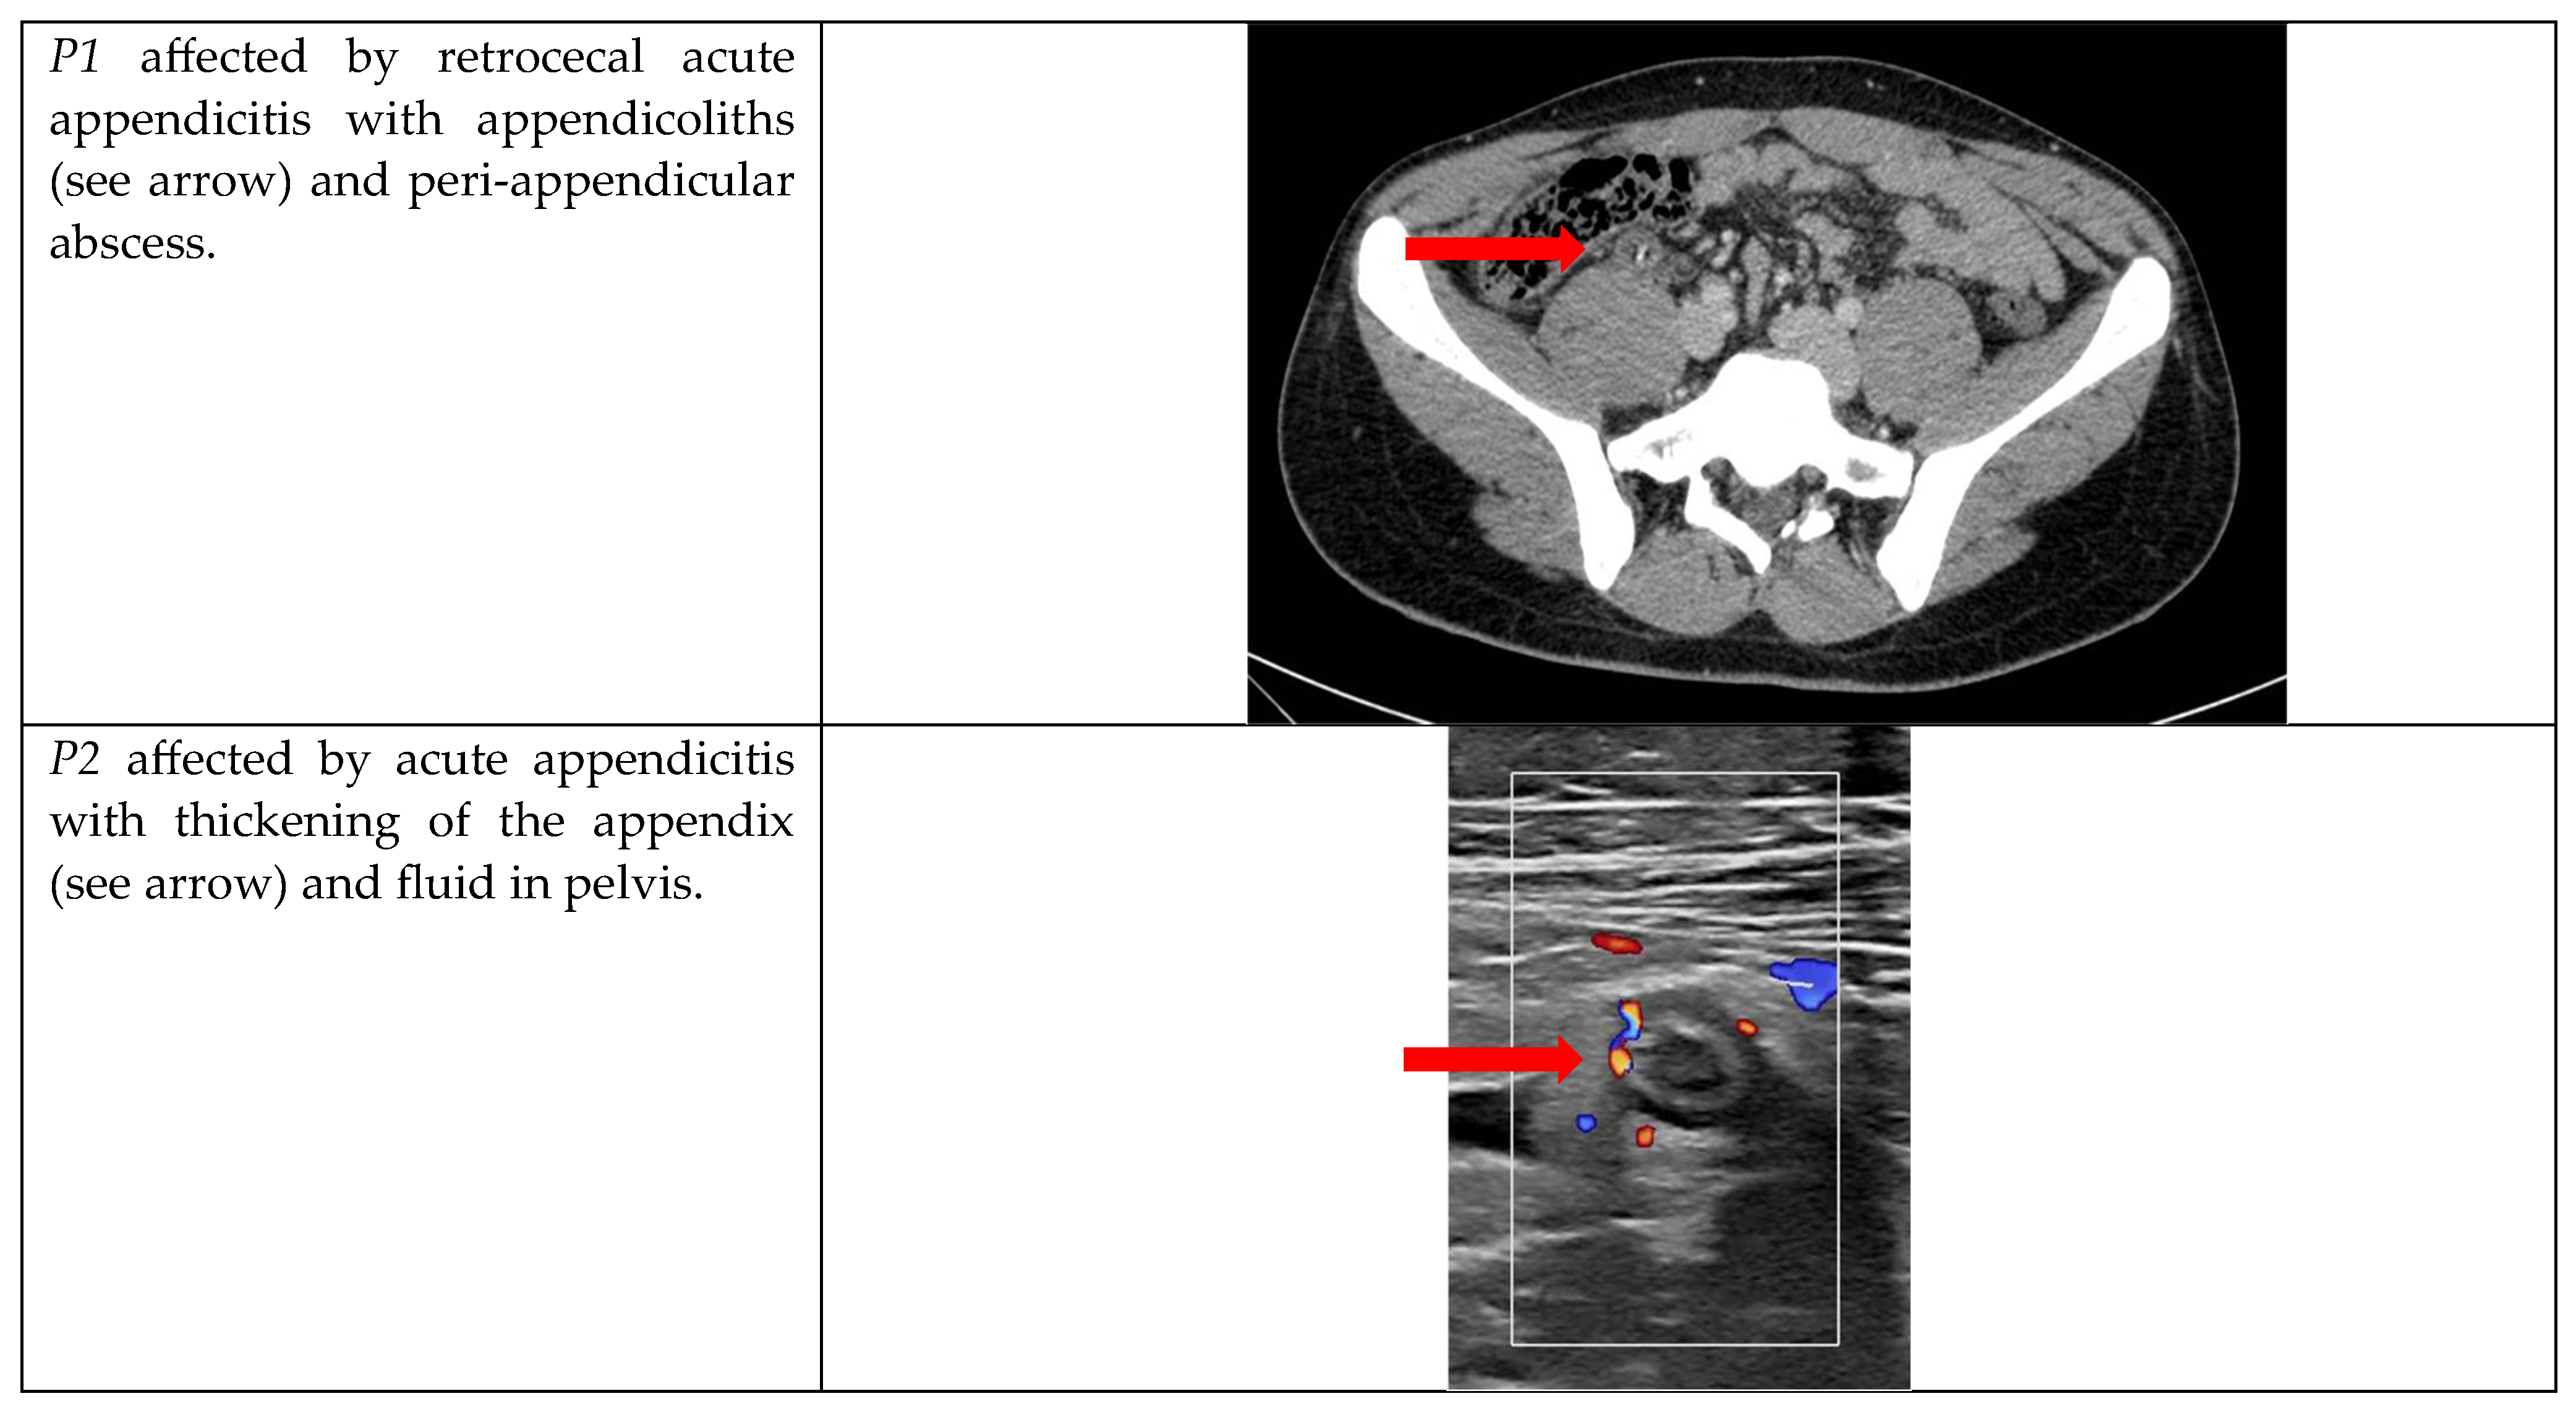

| P1 | M | 20 years | 24.7 | WBC 17.14 109/L, CRP 0.08 mg/dL | No | Caucasian |

| P2 | F | 18 years | 29.8 | WBC 19.55 109/L, CRP 3.52 mg/dL | No | Caucasian |